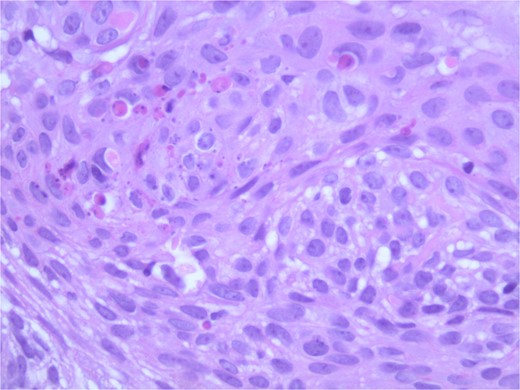

At the time of the surgery, the lesion was excised with 5 mm margins, given the acceptable margins of 4 mm for nonmelanoma skin cancer [4]. Macroscopic examination of the lesion revealed a well-defined, hyperpigmented, macular lesion with pathology positive for infiltrating BSC with negative margins confirmed on histology. Histology was notable for predominantly basal cell morphology with areas of squamous differentiation. The presence of the basal cell carcinoma component is demonstrated (Fig. 1). The BSC with abnormal squamous keratinization is also demonstrated (Figs 2–4). These studies were conducted on routine hematoxylin and eosin stains confirming the diagnosis of BSC. The patient was seen in the office, and at 2 months postoperative, there were no clinical concerns.

Microphotograph revealing BSC with abnormal squamous keratinization on histology.